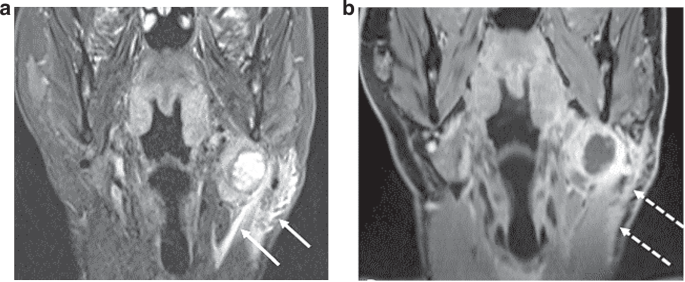

iENE assessment is highly dependent on good quality imaging and we found significant heterogeneity in image quality (especially MRI) in the PATHOS cohort, with 18.6% of images acquired over the 9-year recruitment period being deemed suboptimal. The two centres where staging scans were performed in a small number of centralised, high-volume sites had a significantly lower rate of suboptimal imaging than the third centre where imaging was performed across a larger number of referral sites. Factors affecting image quality include post-contrast slice thickness and multiplanar image analysis. These differences are rarely due to different MRI or CT protocols but rather a combination of factors including system quality, radiographic technique and radiologist supervision. Major pENE, defined as >2 mm ENE, may not be reliably detected with imaging slice thickness ≥3 mm due to partial volume artefact (averaging of signal from adjacent small structures into single voxel), and minor pENE ( ≤ 2 mm) will be missed altogether. Furthermore, as lymph nodes in the deep cervical chain are aligned longitudinally along the jugular vein, nodal coalescence will tend to occur along this axis, thus multiplanar assessment of both coronal and sagittal images is needed to accurately identify nodal coalescence (iENE grade 2). Iatrogenic changes are another confounder and 38% of study cases (111 patients) underwent a core nodal biopsy prior to their staging CT and/or MRI scans. Knowing if and when a core biopsy has been carried out is imperative before cross-sectional imaging is reviewed for iENE, as iatrogenic biopsy effects can vary from minimal perinodal fat-stranding to changes that mimic grade 3 iENE, examples of which are shown in Figs. 4 and 5. Following the 1st round of radiology reviews, it was agreed that any potential biopsy-related changes should be discounted and not recorded as iENE for the 2nd (final) round reviews, following general TNM principles (14). This obviously has a potential for producing false negative results where genuine iENE features are masked by iatrogenic change and we saw the highest proportion of recent (<30 day) core biopsies in the iENE-/pENE+ group. Conversely core biopsy may also produce false positives if biopsy related findings are interpreted as positive iENE features, particularly if the reporting radiologist is unaware of recent biopsy (Figs. 4 and 5).